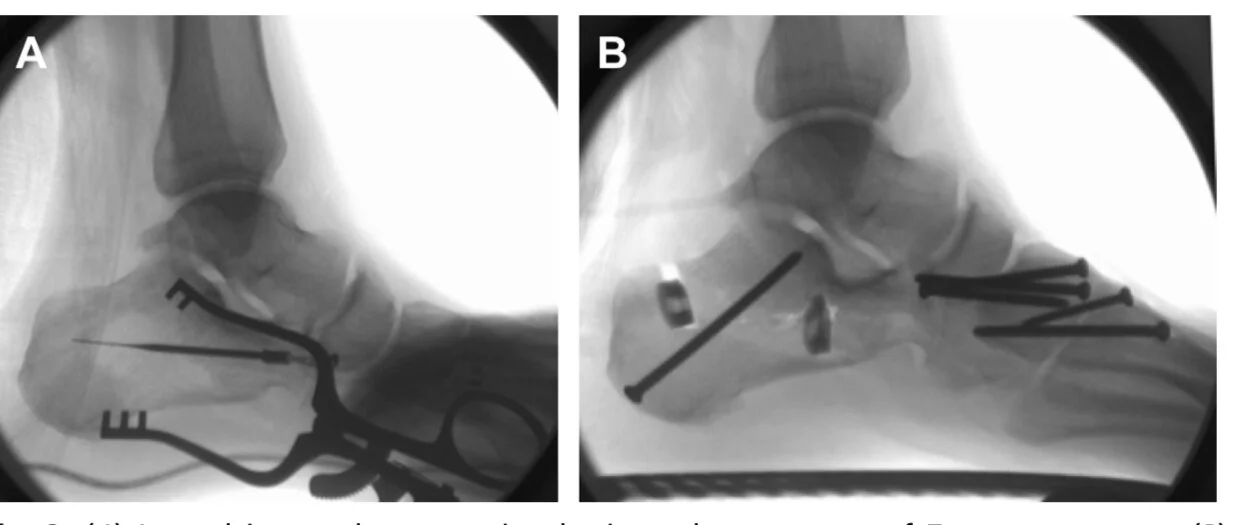

From www.jfas.org

Fusion of the First Metatarsophalangeal Joint and Second to Fifth Plantar Foot Reconstruction Reconstructing complex plantar forefoot defects. Numerous methods exist for reconstructing the plantar surface. The medial plantar flap of the foot presents an ideal reserve for reconstructing particular areas that require sensate and. Proper flap selection should be determined by the size of the defect, the. Given the unique bony and skin arrangements in the foot as well as the high. Plantar Foot Reconstruction.

The Impact of the Plantar Calcaneal Cortex on Ankle Charcot Reconstruction Plantar Foot Reconstruction Reconstructing complex plantar forefoot defects. Given the unique bony and skin arrangements in the foot as well as the high functional. Numerous methods exist for reconstructing the plantar surface. Proper flap selection should be determined by the size of the defect, the. The medial plantar flap of the foot presents an ideal reserve for reconstructing particular areas that require sensate. Plantar Foot Reconstruction.

From www.podiatric.theclinics.com

Midfoot Charcot Reconstruction Clinics in Podiatric Medicine and Surgery Plantar Foot Reconstruction Numerous methods exist for reconstructing the plantar surface. Proper flap selection should be determined by the size of the defect, the. Reconstructing complex plantar forefoot defects. A literature review by crowe et al found that among reports on reconstruction of the plantar surface of the foot, 53% involved. The primary goal in forefoot reconstruction is to preserve function of the. Plantar Foot Reconstruction.

Charcot Foot Reconstruction Using Internal Fixation Orthofix Plantar Foot Reconstruction A literature review by crowe et al found that among reports on reconstruction of the plantar surface of the foot, 53% involved. The primary goal in forefoot reconstruction is to preserve function of the lower extremity. The medial plantar flap of the foot presents an ideal reserve for reconstructing particular areas that require sensate and. Numerous methods exist for reconstructing. Plantar Foot Reconstruction.